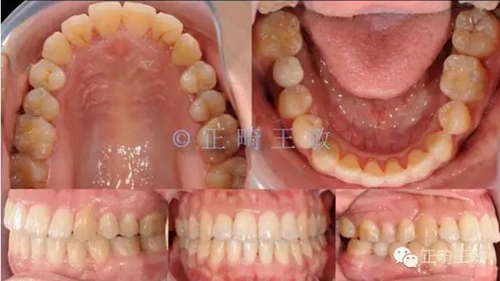

雖然這個(gè)時(shí)候正畸并沒(méi)有結(jié)束,但對(duì)于種植來(lái)說(shuō),間隙和排列,已經(jīng)足夠了,畢竟種植周期也要4個(gè)月,后面的治療就是繼續(xù)關(guān)閉間隙,調(diào)整咬合,同時(shí)等著那顆種植牙生根發(fā)芽。來(lái)看看最終的樣子:

10.jpg

一年后復(fù)查,沒(méi)有任何問(wèn)題。